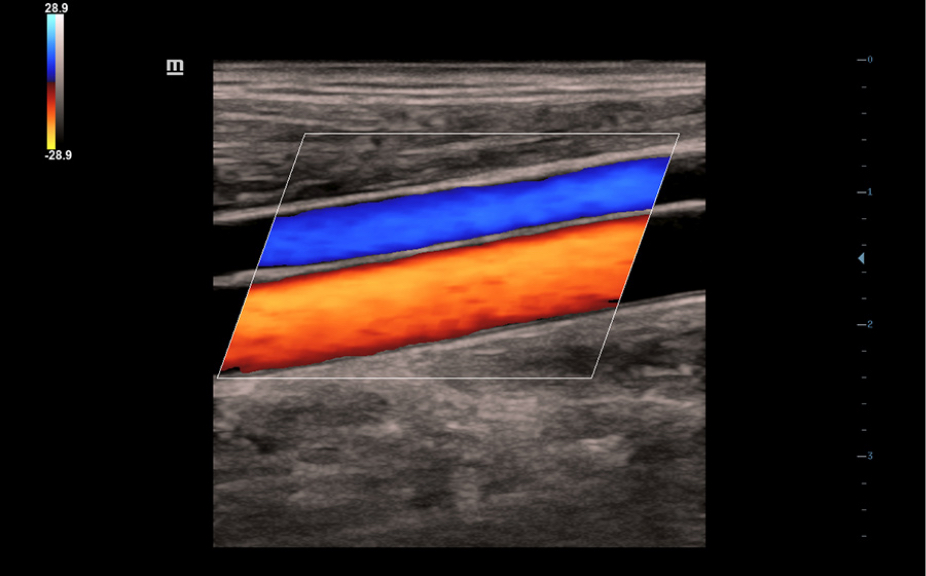

Sistema de diagnĂłstico ecogrĂĄfico

DC- 30

AtenciĂłn primaria con una excelente visiĂłn

FullHD

ImĂĄgenes clĂnicas